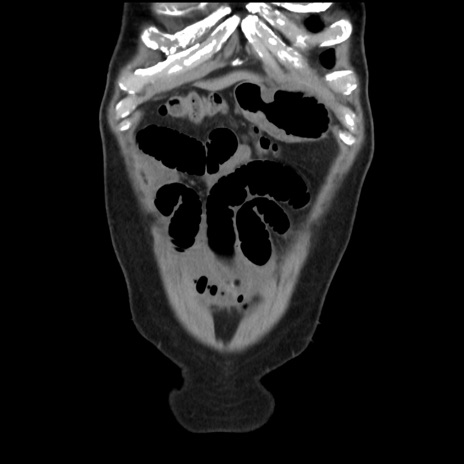

横断像

【症例】 70歳代男性

【主訴】 腹痛、嘔吐

【現病歴】 約1ヶ月前より間欠的に腹痛と嘔吐あり、当院消化器内科を受診したところCTで多発する肝臓のLDAを指摘され、精査中であった。以降は消化器症状は安定していたが、2日前より嘔気と腹痛があり、同日より排便・排ガスが消失した。改善認めず、 本日、救急外来を受診した。

【既往歴】 大腸ポリープ切除後。

【身体所見】意識清明・会話良好、BT 36.3℃、BP 127/80mmHg、 P 80bpm、腹部:膨満あり、平坦・軟、上腹部正中および下腹部正中に圧痛あり、反跳痛なし、筋性防御なし。

【データ】WBC 7200、CRP 0.77